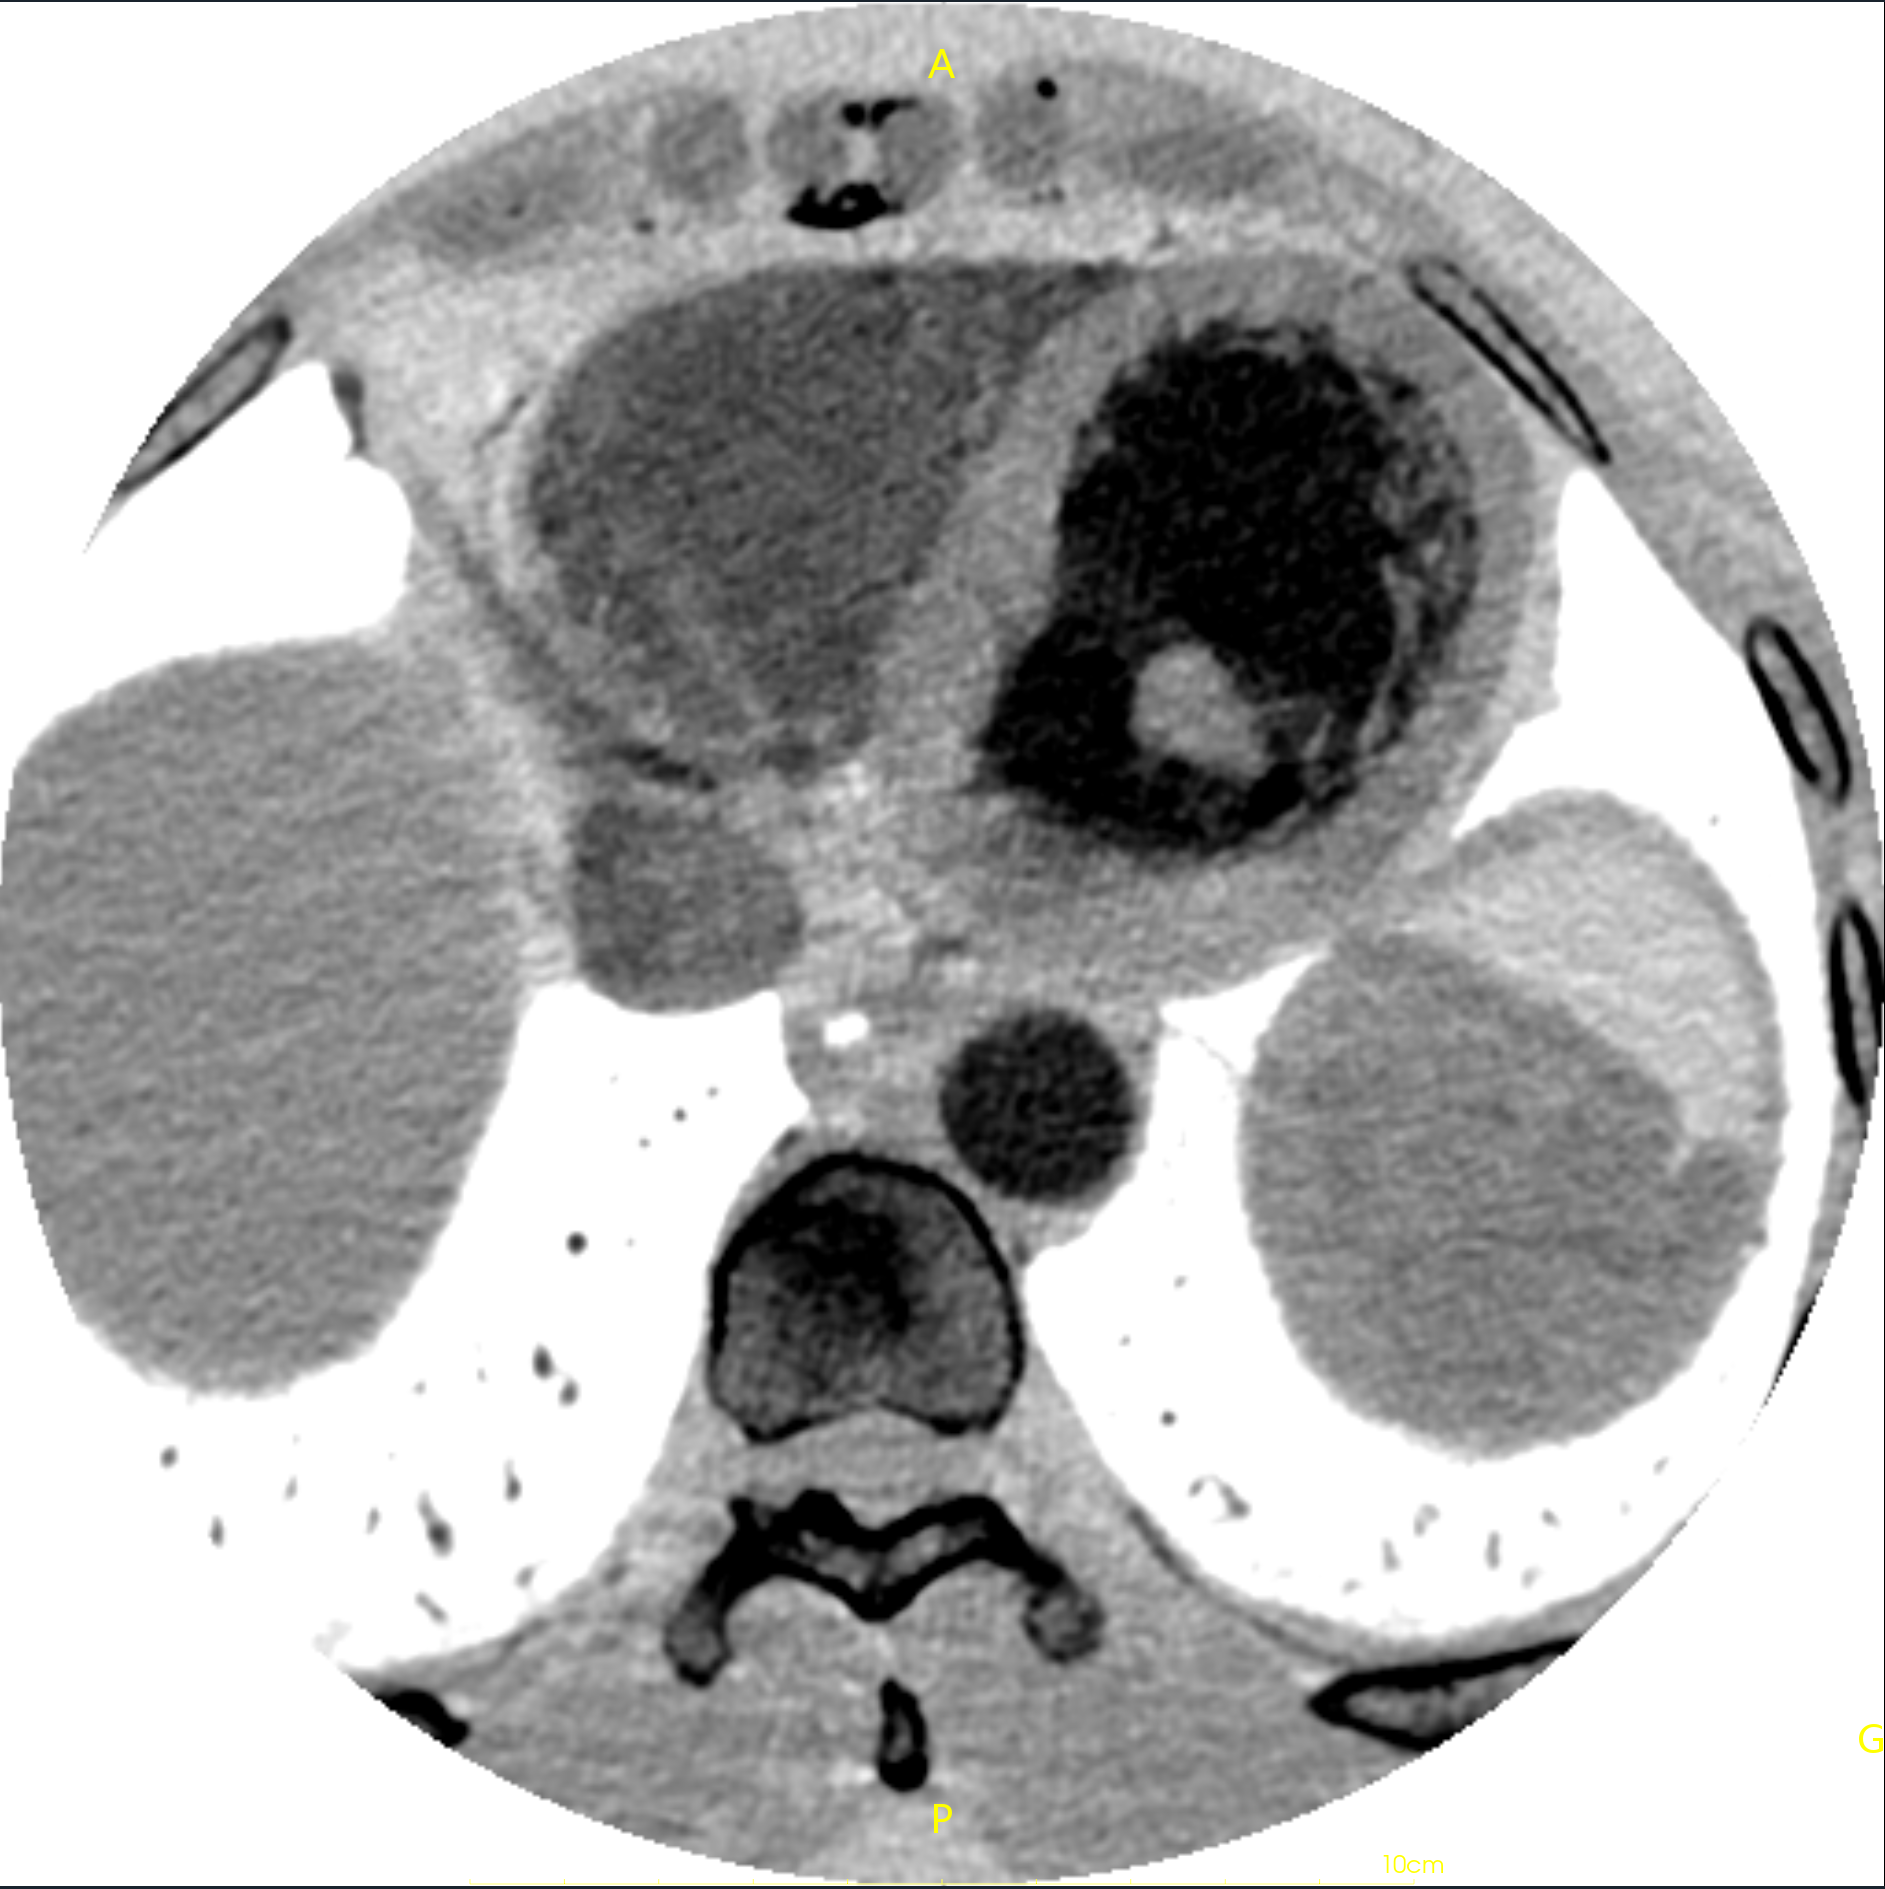

https://blog.csdn.net/liushao1031177/article/details/117696381 如果遇到下面这种有明显边界的ct影像,如何才能区分哪些是有效的CT值,哪些是背景值?

我们可以根据0028,0103内值来区分图像是否被填充过,如果pixel representation为0,则该CT图像未被填充过,其内部像素值都表示有效CT数值;如果pixel representation为1,则该CT图像内有两部分CT值,一部分是有效CT值,另一部分是填充值,只是为了把图像展示成矩形图像;

由于图像的斜率为1.0,截距为-1024,则-2000就会在线性变换后为-3024;

找一个背景值,可以看到该值为-3024;则像素值为-3024的像素即为填充像素,可以在后处理中过滤掉;